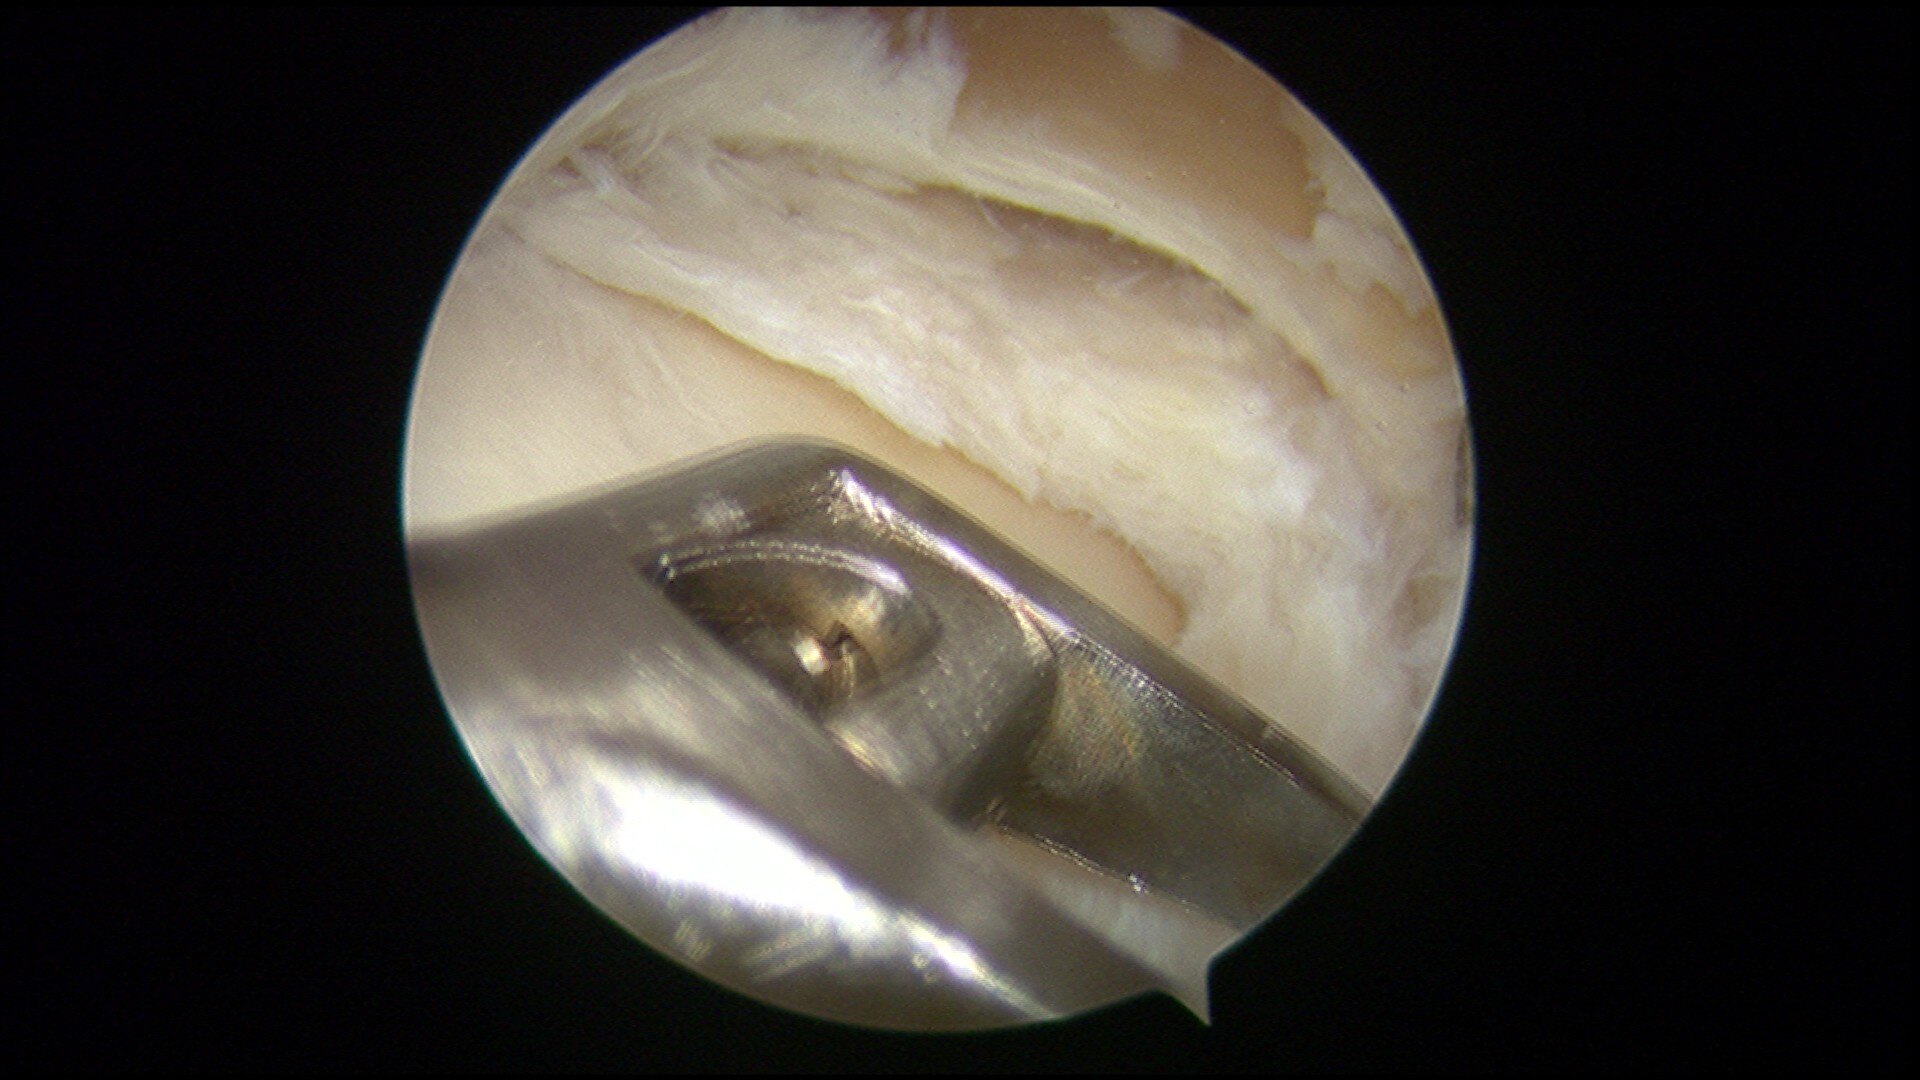

盘状半月板成形手术